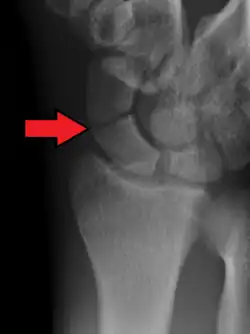

-

A subtle scaphoid fracture -

A more obvious scaphoid fracture on a scaphoid view X ray -

Radiolucency around a 12 days old scaphoid fracture that was initially barely visible.[13]